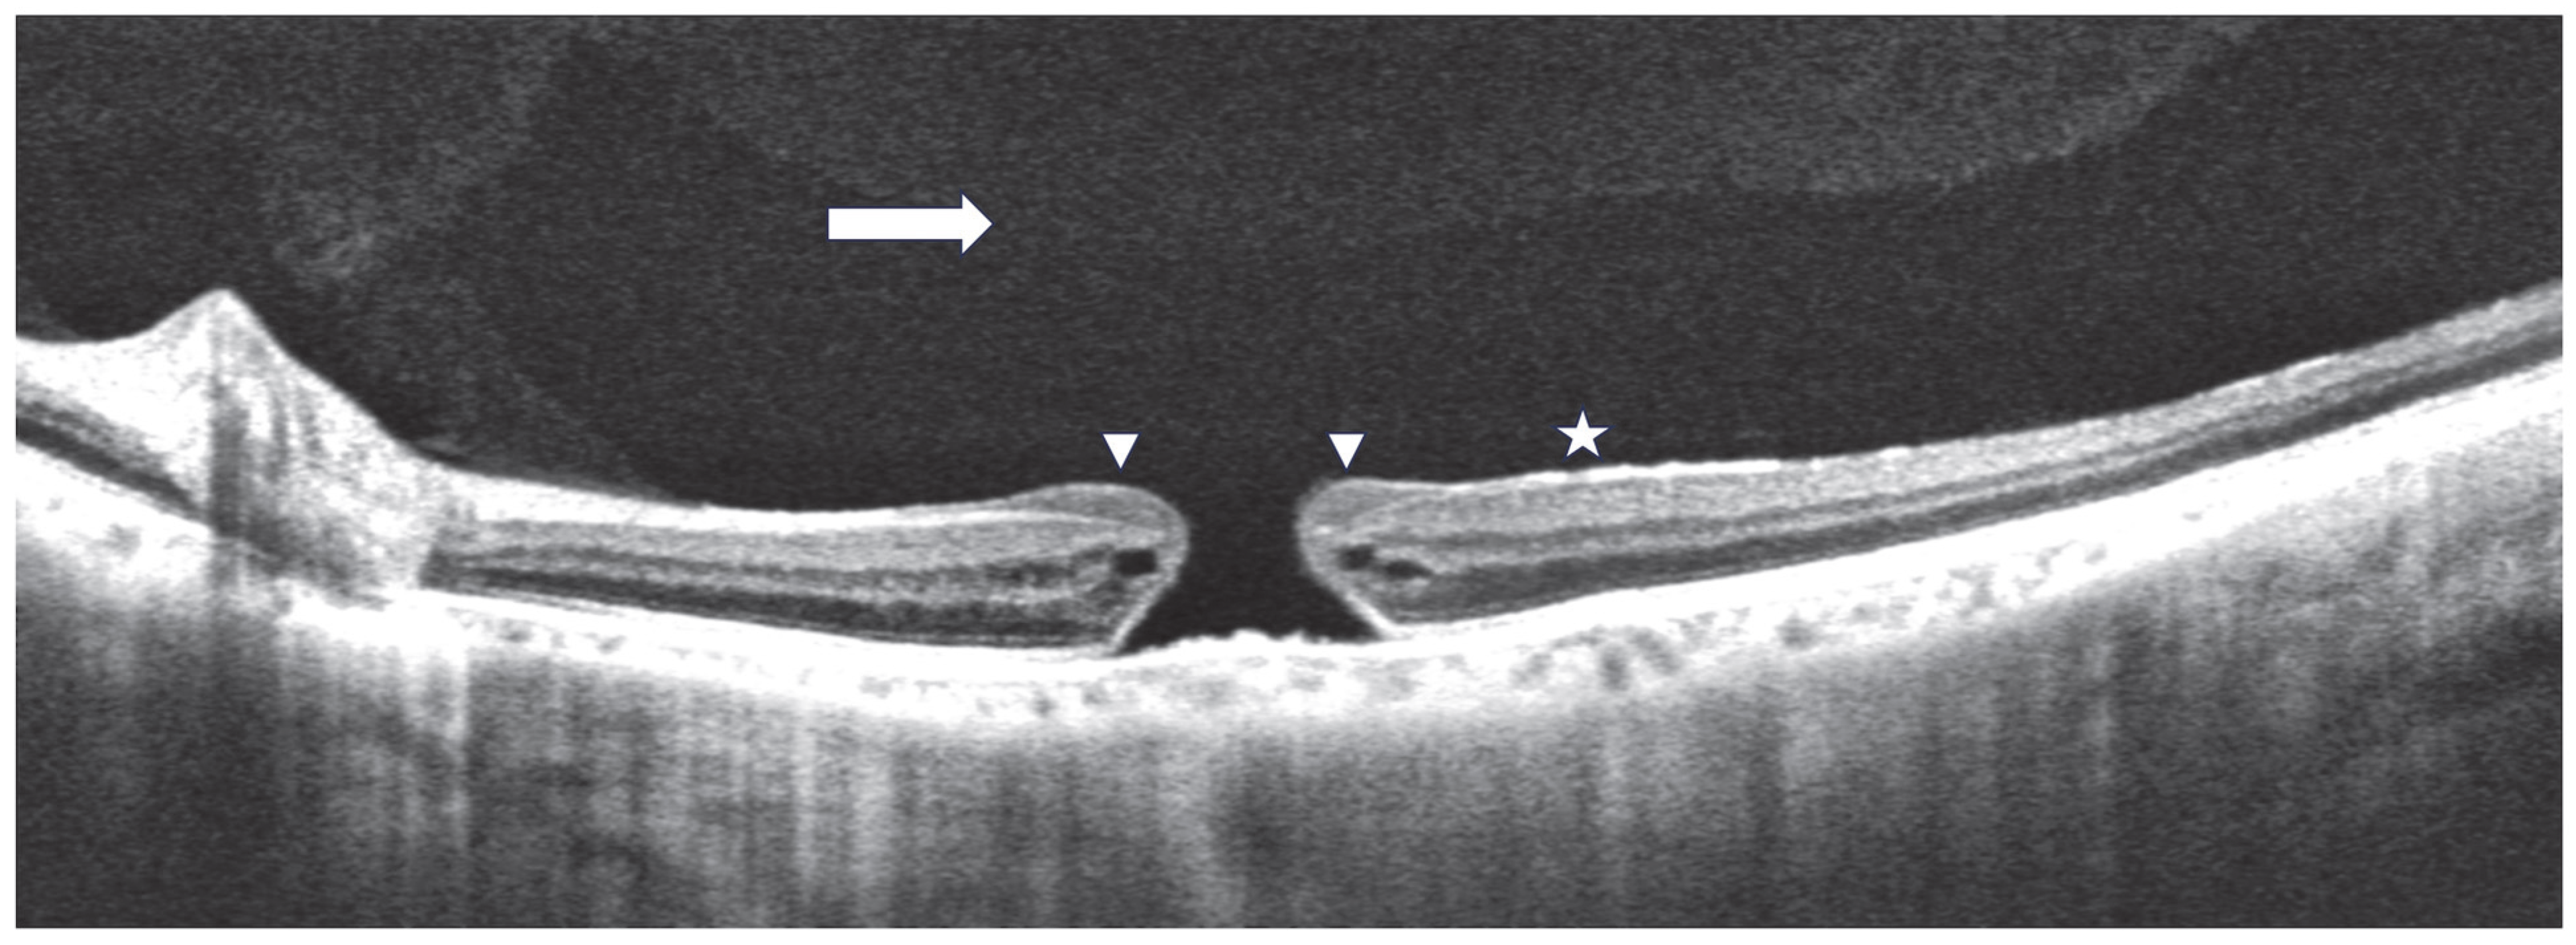

1. Introduction

2.2. Clinical Characteristics and Clinical Course of FTMHs